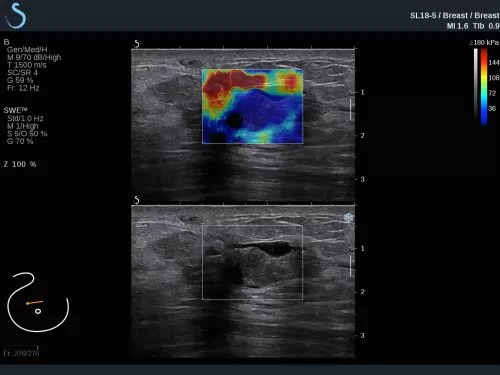

Τις μοναδικές δυνατότητες της ShearWave ελαστογραφιας (SWE) του υπερηχογράφου Aixplorer Ultimate μπορείτε να γνωρίσετε από κοντά στα workshop που θα πραγματοποιηθούν στις 29/9/2018 κατά τη διάρκεια της Ημερίδας Υπερηχογραφίας – Ελαστογραφιας Μαστών.

Δείτε πώς με την SWE μπορείτε να αυξήσετε την ευαισθησία και ειδικότητα του υπερηχογραφήματος, την προγνωστική αξία της Βιοψίας αλλά και το πως μπορεί να αναβαθμιστεί ένα DCIS σε IDC.